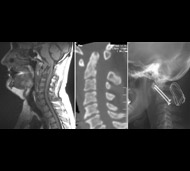

- Рентгенография. Медработники обычно проводят это исследование всем пострадавшим от травмы, у кого есть подозрение на повреждение спинного мозга. Рентген может выявить проблемы с позвонками, опухоли, переломы или дегенеративные изменения в позвоночнике.

- Компьютерная томография (КТ). КТ может предоставить лучшее изображение патологии, видимой на рентгеновских снимках. Этот вид обследования использует компьютер, чтобы воссоздать серию изображений поперечного сечения, которые могут выявить проблемы, связанные с костями, дисками и другие проблемы

- Магнитно-резонансная томография (МРТ). МРТ использует магнитную силу и радиоволны, чтобы воспроизвести изображения, полученные через компьютер. Этот тест очень помогает в ситуациях, когда необходимо рассмотреть спинной мозг и выявить грыжу межпозвоночного диска, сгустки крови и другие образования, которые могут сдавливать спинной мозг. Но МРТ нельзя проводить пациентам с сердечными водителями ритма или пострадавшим, которым необходима аппаратура, поддерживающая жизнедеятельность организма или приспособление для вытягивания шейного отдела позвоночника.

Цель операции – стабилизация позвоночника металлическими конструкциями (имплантантами). Наша клиника была первой в СНГ, кто применил современные конструкции при переломах позвоночника. Сейчас мы используем импортные конструкции типа CD Horison Legacy (США), Atlantis (США), Sextant (США), Socore (Франция). Операции требуют сложной рентгеновской техники и специального инструментария. При неосложненных переломах позвоночника больные могут ходить после таких операций уже на второй - третий день после операции. Также в Международном центре нейрохирургии впервые в Украине был внедрен метод миниинвазивных операций при переломах позвоночника.